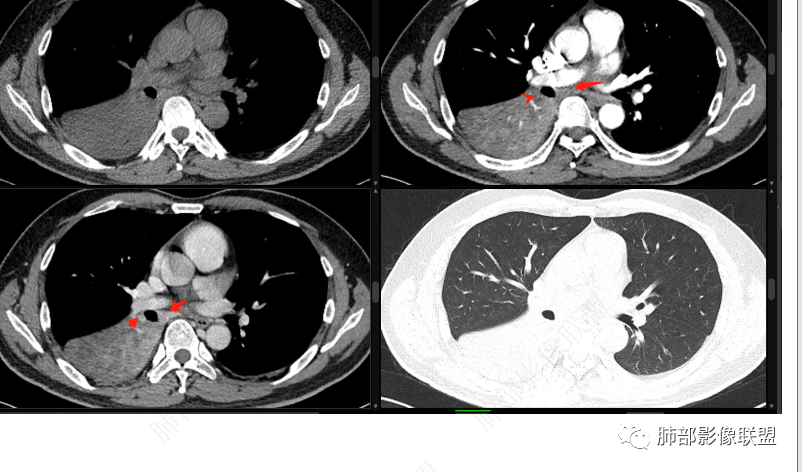

右肺下叶实变影,局部膨隆,边缘磨玻璃密度影,肺门区域明显强化考虑恶性,腺癌可能。

右肺下叶实变表现,强化和形态不考虑门口堵所致不张,枯树枝不明显,整个肺叶考虑肿瘤浸润,首先要考虑腺癌

右肺下叶实变,周围磨玻璃,近端支气管扩张,管壁凹凸不平,远端阻塞,可见粘液栓,不均匀强化,有低密度无强化影,其内血管显示尚可,考虑粘液腺癌,鉴别淋巴瘤

右下叶支气管结节,明显强化,远离支气管内粘液栓及肺不张,考虑肿瘤——类癌?涎腺肿瘤?鳞癌?强化明显,类癌可能性更大一些。

右肺下叶阻塞性肺不张,粘液栓,边缘磨玻璃影,良性,谈栓,异物,恶,鳞,腺癌,类癌,男性,46岁,病程不长,似乎有强化,选类癌。

右下叶肿块外向内生长,支气管阻塞伴阻塞性炎症,不均匀强化,血管边缘模糊,考虑腺癌,鉴别类癌。

右肺下叶大片实变,密度不均匀,可见支气管充气征及粘液区,右肺下叶支气管内结节影,下叶支气管阻塞,病灶前下可见磨玻璃影,右侧积液,考虑粘液腺癌,鉴别类癌?

右下叶支气管狹窄,内见高密度强化结节,远端大片不张实变,实变内可见多发粘液拴,整体观察实变似有见缝就针的感觉,综和分析考虑粘液表皮样癌,其次考虑类癌

中央型肿瘤pk周围型肿瘤  。壮年男性,热咳一周伴气喘,中性白细胞升高,临床是个感染过程。支持中央型病变的证据:1  肺门明显强化结节 2 横s征  3 支气管粘液栓  4 主支气管变窄,似见冰山征      支持周围型病变:1 按叶段塑形  2 血管造影征  3 病灶内弥漫高强化  4 周围伴磨玻璃灶,但境界不清继发感染?误吸?综合 中央型肿瘤可能大:类癌》鳞癌

右肺下叶不张,右下肺门区高强化结节,似乎呈冰山征,首先考虑类癌可能

右下肺门似见一结节影,明显强化,远端支气管黏液栓,右肺下叶不张,考虑类癌,次之黏液表皮样癌 腺样囊腺癌

右肺下叶支气管见结节灶继发右肺下叶膨胀不全,右肺中央局部炎性改变,下叶支气管结节动脉期明星强化,静脉期强化减低,首先考虑肺鳞癌,鉴别类癌、粘液表皮样癌。

首先血管未见明显侵犯、移位,提示病灶:炎性;肿瘤:外朝内——含粘液类腺癌(肺门淋巴结转移),腔内肿瘤(鳞癌、腺癌、类癌、小细胞、粘液表皮等)

从强化看:外周密度低,强化弱

就不太符合腔内肿瘤远端不张的表现,因为外围不张——强化明显

这一例反了

按这个特点周围要考虑肿瘤组织

腔内肿瘤,远端堵塞

CT提示1、右肺下叶气管堵塞伴阻塞性肺不张,肺炎征象。2、破坏气管周边肿物可见结节样,肿物整体呈团块样

3、增强可见肿物明显强化。4、肿瘤内部血管可见破坏征象,但是破坏不完全。5.肿物坏死征象不明显。